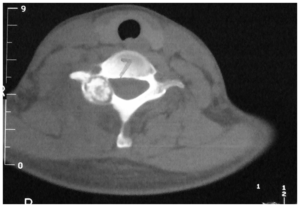

Osteoid osteoma is a benign bone tumor that occurs predominantly in children and adolescents. They typically have lucrative nidus (usually 1.5-2 cm in size) and an osteosclerotic margin. Osteoid osteomas of the spine, most often located in the lumbar part, represent approximately 10% of all osteoid osteomas - primarily these tumors occur in the long bones (most often the femur, tibia). [12]

Spinal osteoid osteomas in the vast majority cause painful scoliosis, concavely on the lesion side, vertebral deformities create compression on the spinal cord. The therapy is surgical, or radiofrequency ablation is used. [13][14] náhled|CT – spinální osteoblastom